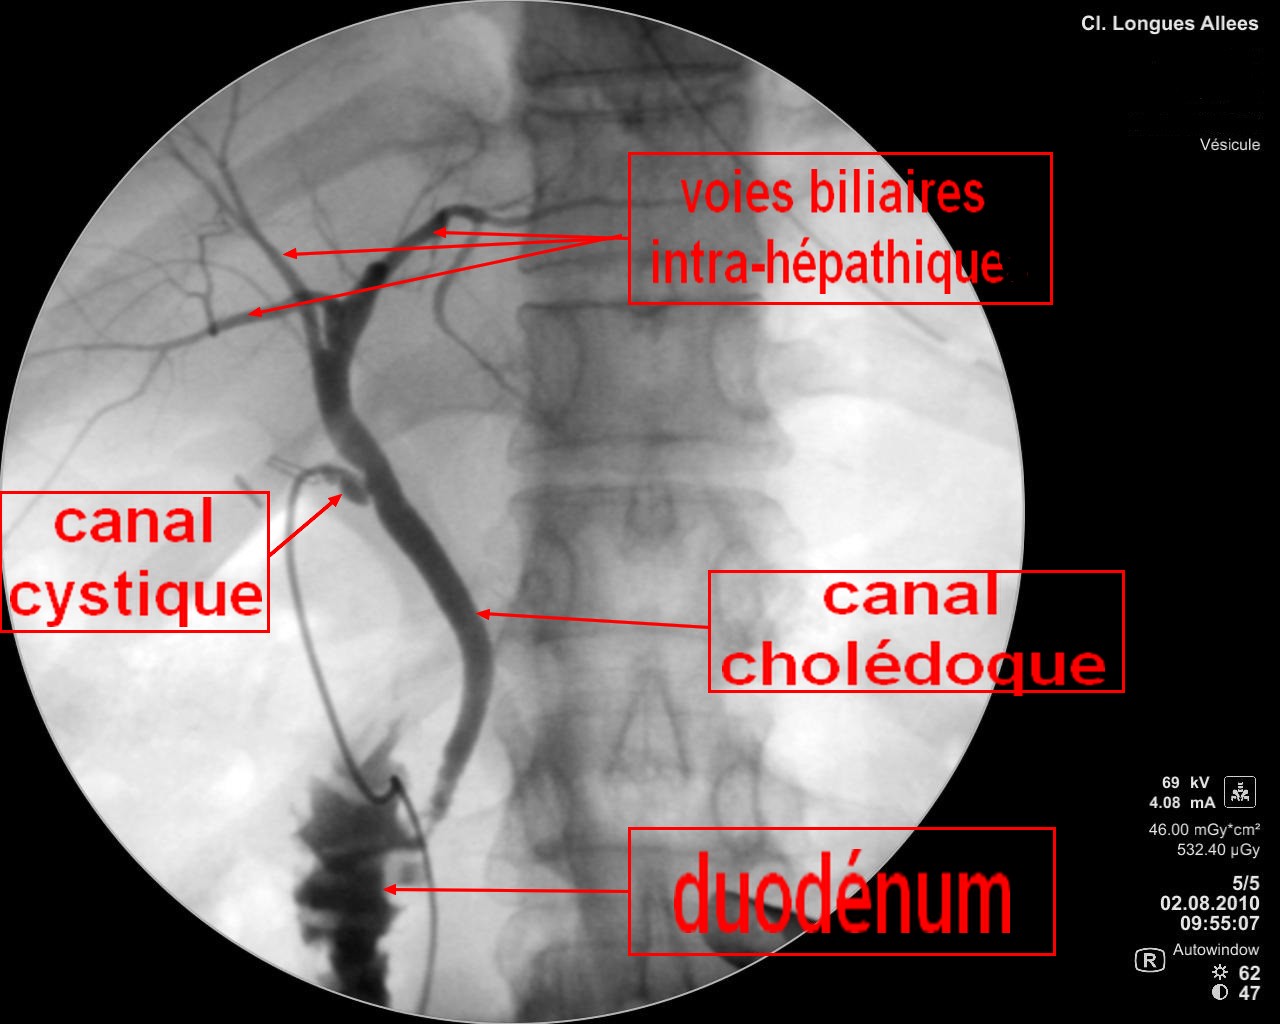

Tout savoir sur l'ablation de la vésicule biliaire. L'ablation de la vésicule biliaire, également appelée cholécystectomie est une intervention chirurgicale régulièrement pratiquée qui vise à retirer la vésicule biliaire. Cet organe en forme de poire situé sur le côté droit de l'abdomen, juste sous le foie va servir à.. avoir la diarrhée après une cholécystectomie ou une ablation de la vésicule biliaire, Maintenant quoi?